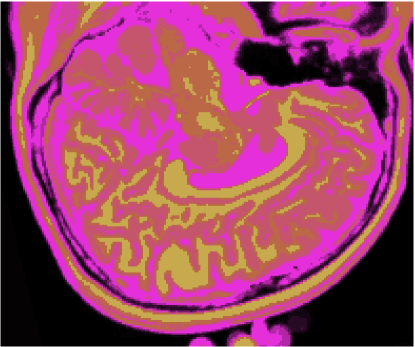

As figuras 2 (banda 0), 3 (banda 1) e 4 (banda 2) mostram a fatia 97 de um volume de imagens sagitais com 181 fatias e 0% de ruído, ponderadas em PD (densidade de próton), T1subscript𝑇1T_{1} e T2subscript𝑇2T_{2}, enquanto a figura 5 ilustra a composição colorida R0-G1-B2 da mesma fatia. Pode-se notar no topo do crânio, na parte inferior das imagens, a presença de artefatos, que podem ser resultantes de erros no simulador, mas que não são prejudiciais à análise, uma vez que, neste trabalho, não é dada ênfase à análise anatômica.

Refer to caption

Figura 5: Composição colorida R0-G1-B2 das imagens da fatia 97 ponderadas em PD, T1subscript𝑇1T_{1} e T2subscript𝑇2T_{2}

3.1 Classificadores Dialéticos Objetivos

A figura 6 mostra os resultados de classificação, enquanto a figura 7 exibe os resultados de quantização para a imagem sem ruído da fatia 97, figura 5, usando os métodos KO, CM, KM, ODC-PME e ODC-CAN. Esses resultados ilustram qualitativamente as diferenças entre os métodos de classificação e quantização, dado que a fatia 97 possui todas as 13 classes presentes na análise [51].

Figura 6: Composição colorida R0-G1-B2 das imagens da fatia 97 ponderadas em PD, T1subscript𝑇1T_{1} e T2subscript𝑇2T_{2} (a) e resultados de classificação usando os métodos KO (b), CM (c), KM (d), ODC-PME (e) e ODC-CAN (f)